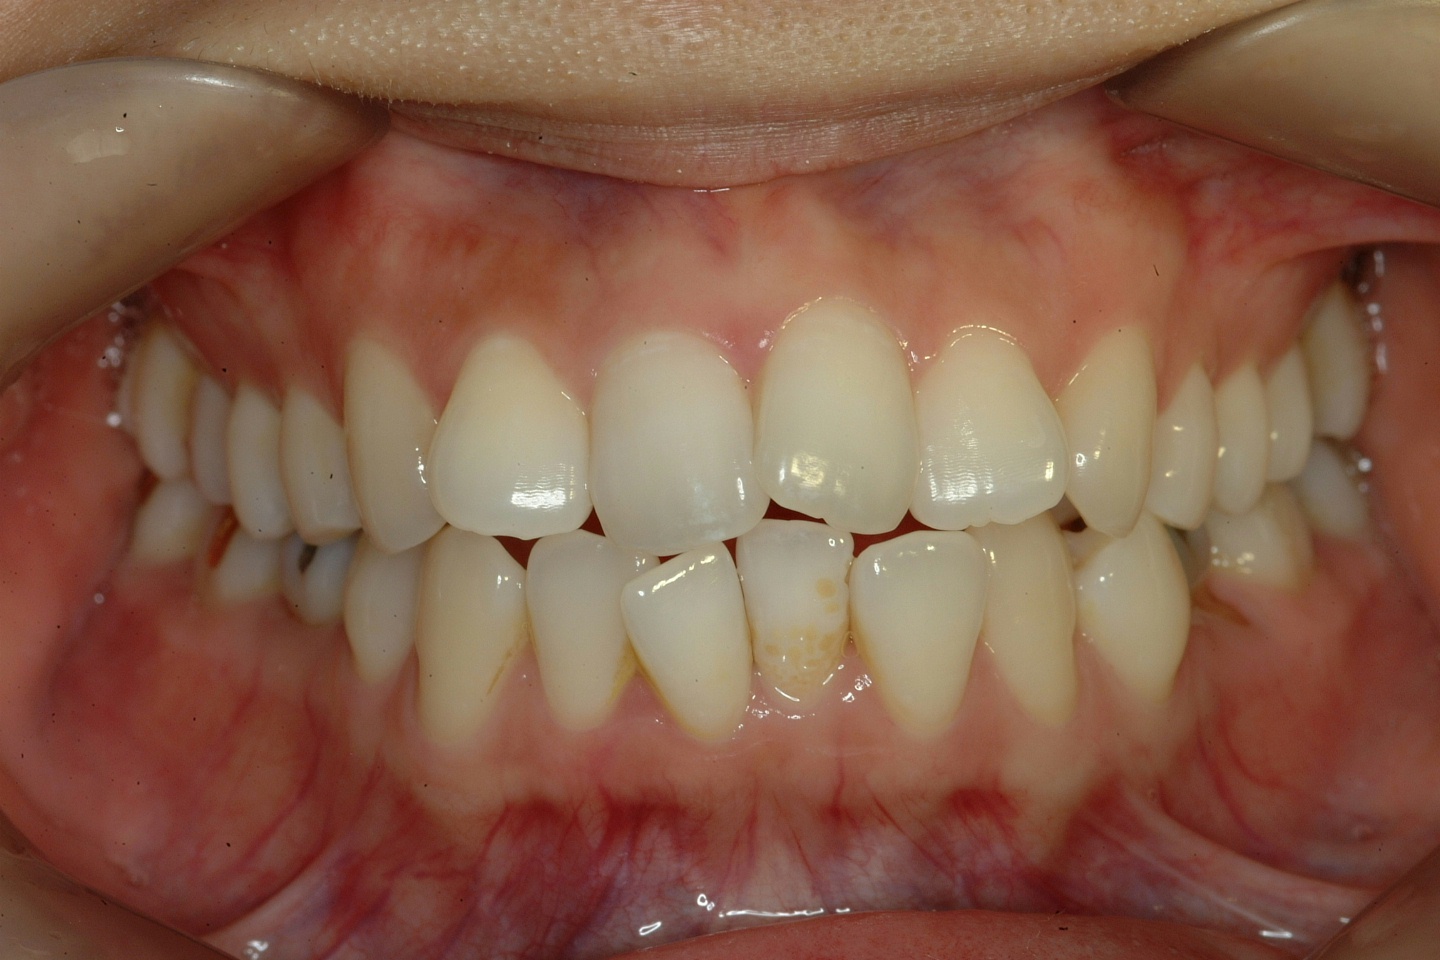

치료 전 사진입니다.